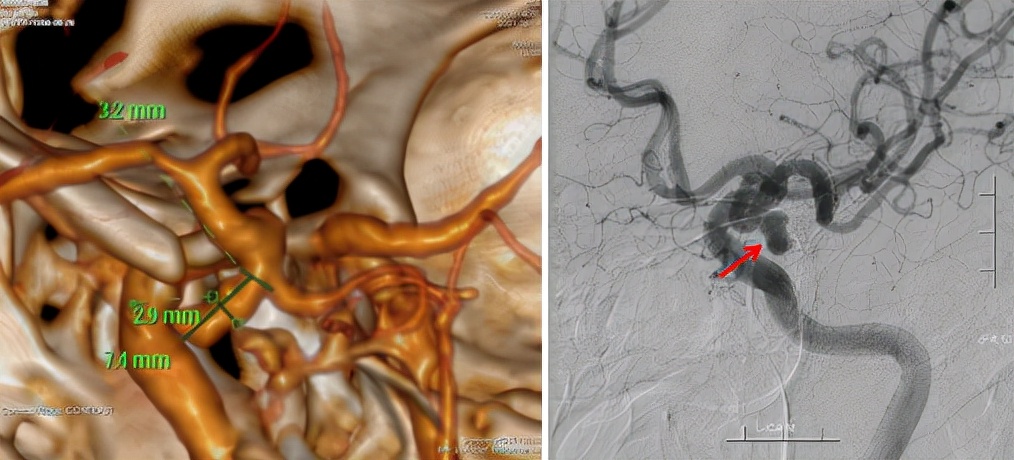

术前影像检查

颅脑DSA血管成像(半球脑动脉)检查结果提示左侧后交通动脉瘤,大小约4.5mm×7.5mm,瘤体朝下、朝内生长。“根据相关检查结果,怀疑患者左侧眼睑下垂为颅内动脉瘤压迫动眼神经受损所致,且目前动脉瘤形态不规则,体积较大,破裂风险较大。”金鑫介绍。